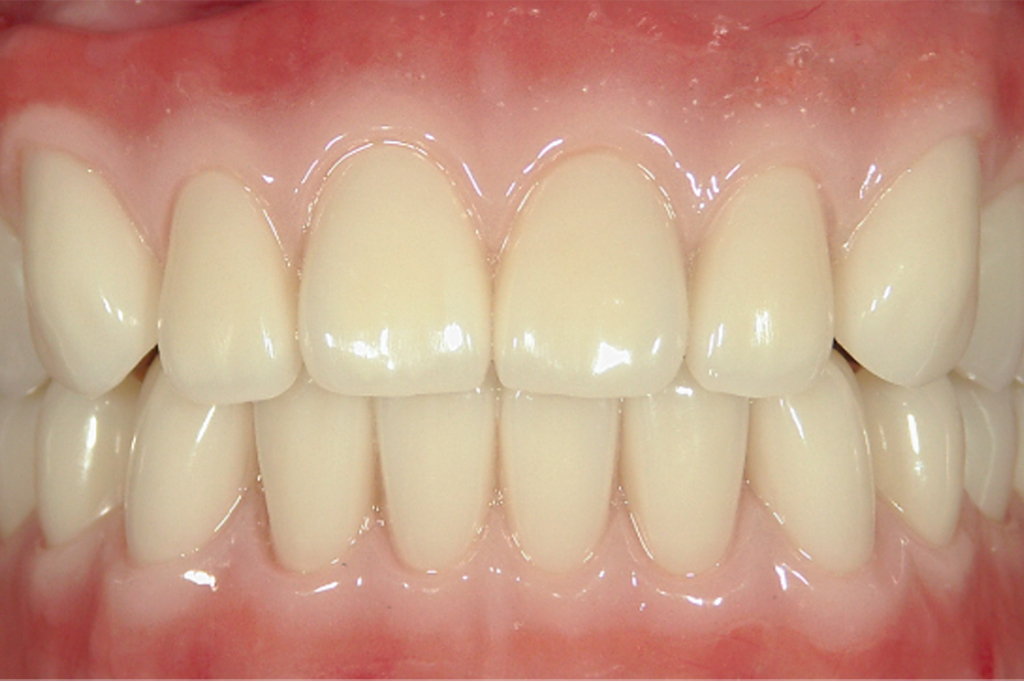

審美加工義歯保険適用外

保険の義歯では既製の人工歯や樹脂を使用するため、見た目が気になる場合があります。

審美加工義歯では、専用の人工歯や樹脂を使用することで、より自然な口元を再現することができ、本来の笑顔につなげることができます。